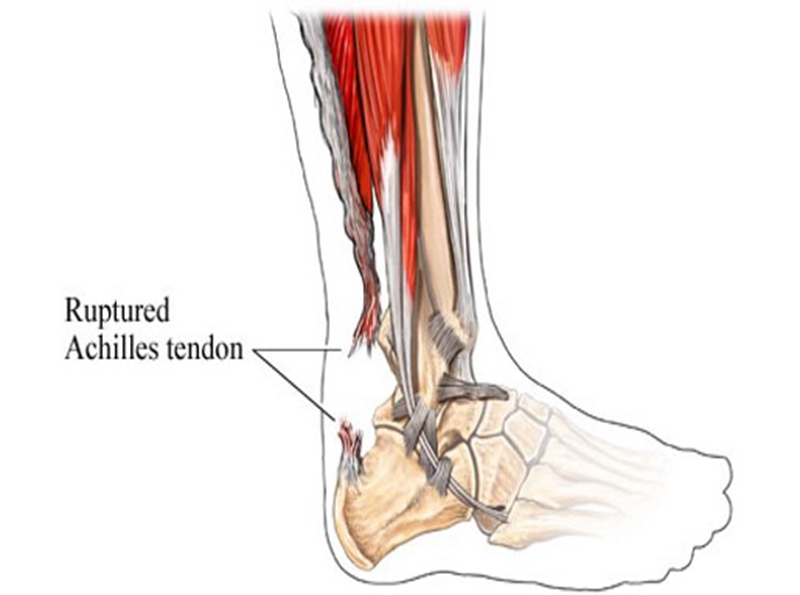

跟腱是人体最长、最强壮的肌腱,起于腓肠肌和比目鱼肌,止于跟骨结节,长约15cm。它在腱的背侧约有4-8层润滑层,位于深筋膜与腱组织之间,每层有独自的营养血管。具有踝关节跖屈,完成脚尖站立、正常走路、跑、跳、上下楼梯等动作的功能。

跟腱断裂容易发生于偶尔参加运动的中年人,所以也称这类人为“周末运动员”。踝在过伸位突然用力,断裂多发生在跟腱止点上方2~6cm,因为跟腱自上而下逐渐变窄增厚,跟骨结节上方2~6cm处最窄,此处最薄弱。

跟腱营养动脉造影显示,下段区域血供相对较少,跟腱中的血管数随年龄的增大而逐渐减少。

症状:跟腱部肿胀、疼痛,足跖屈无力。患者经常诉脚后跟被人踢了一脚,或棒击感。

查体:跟腱连续性中断,局部凹陷,跖屈力量明显减弱,提踵试验阳性,Thompson试验阳性。